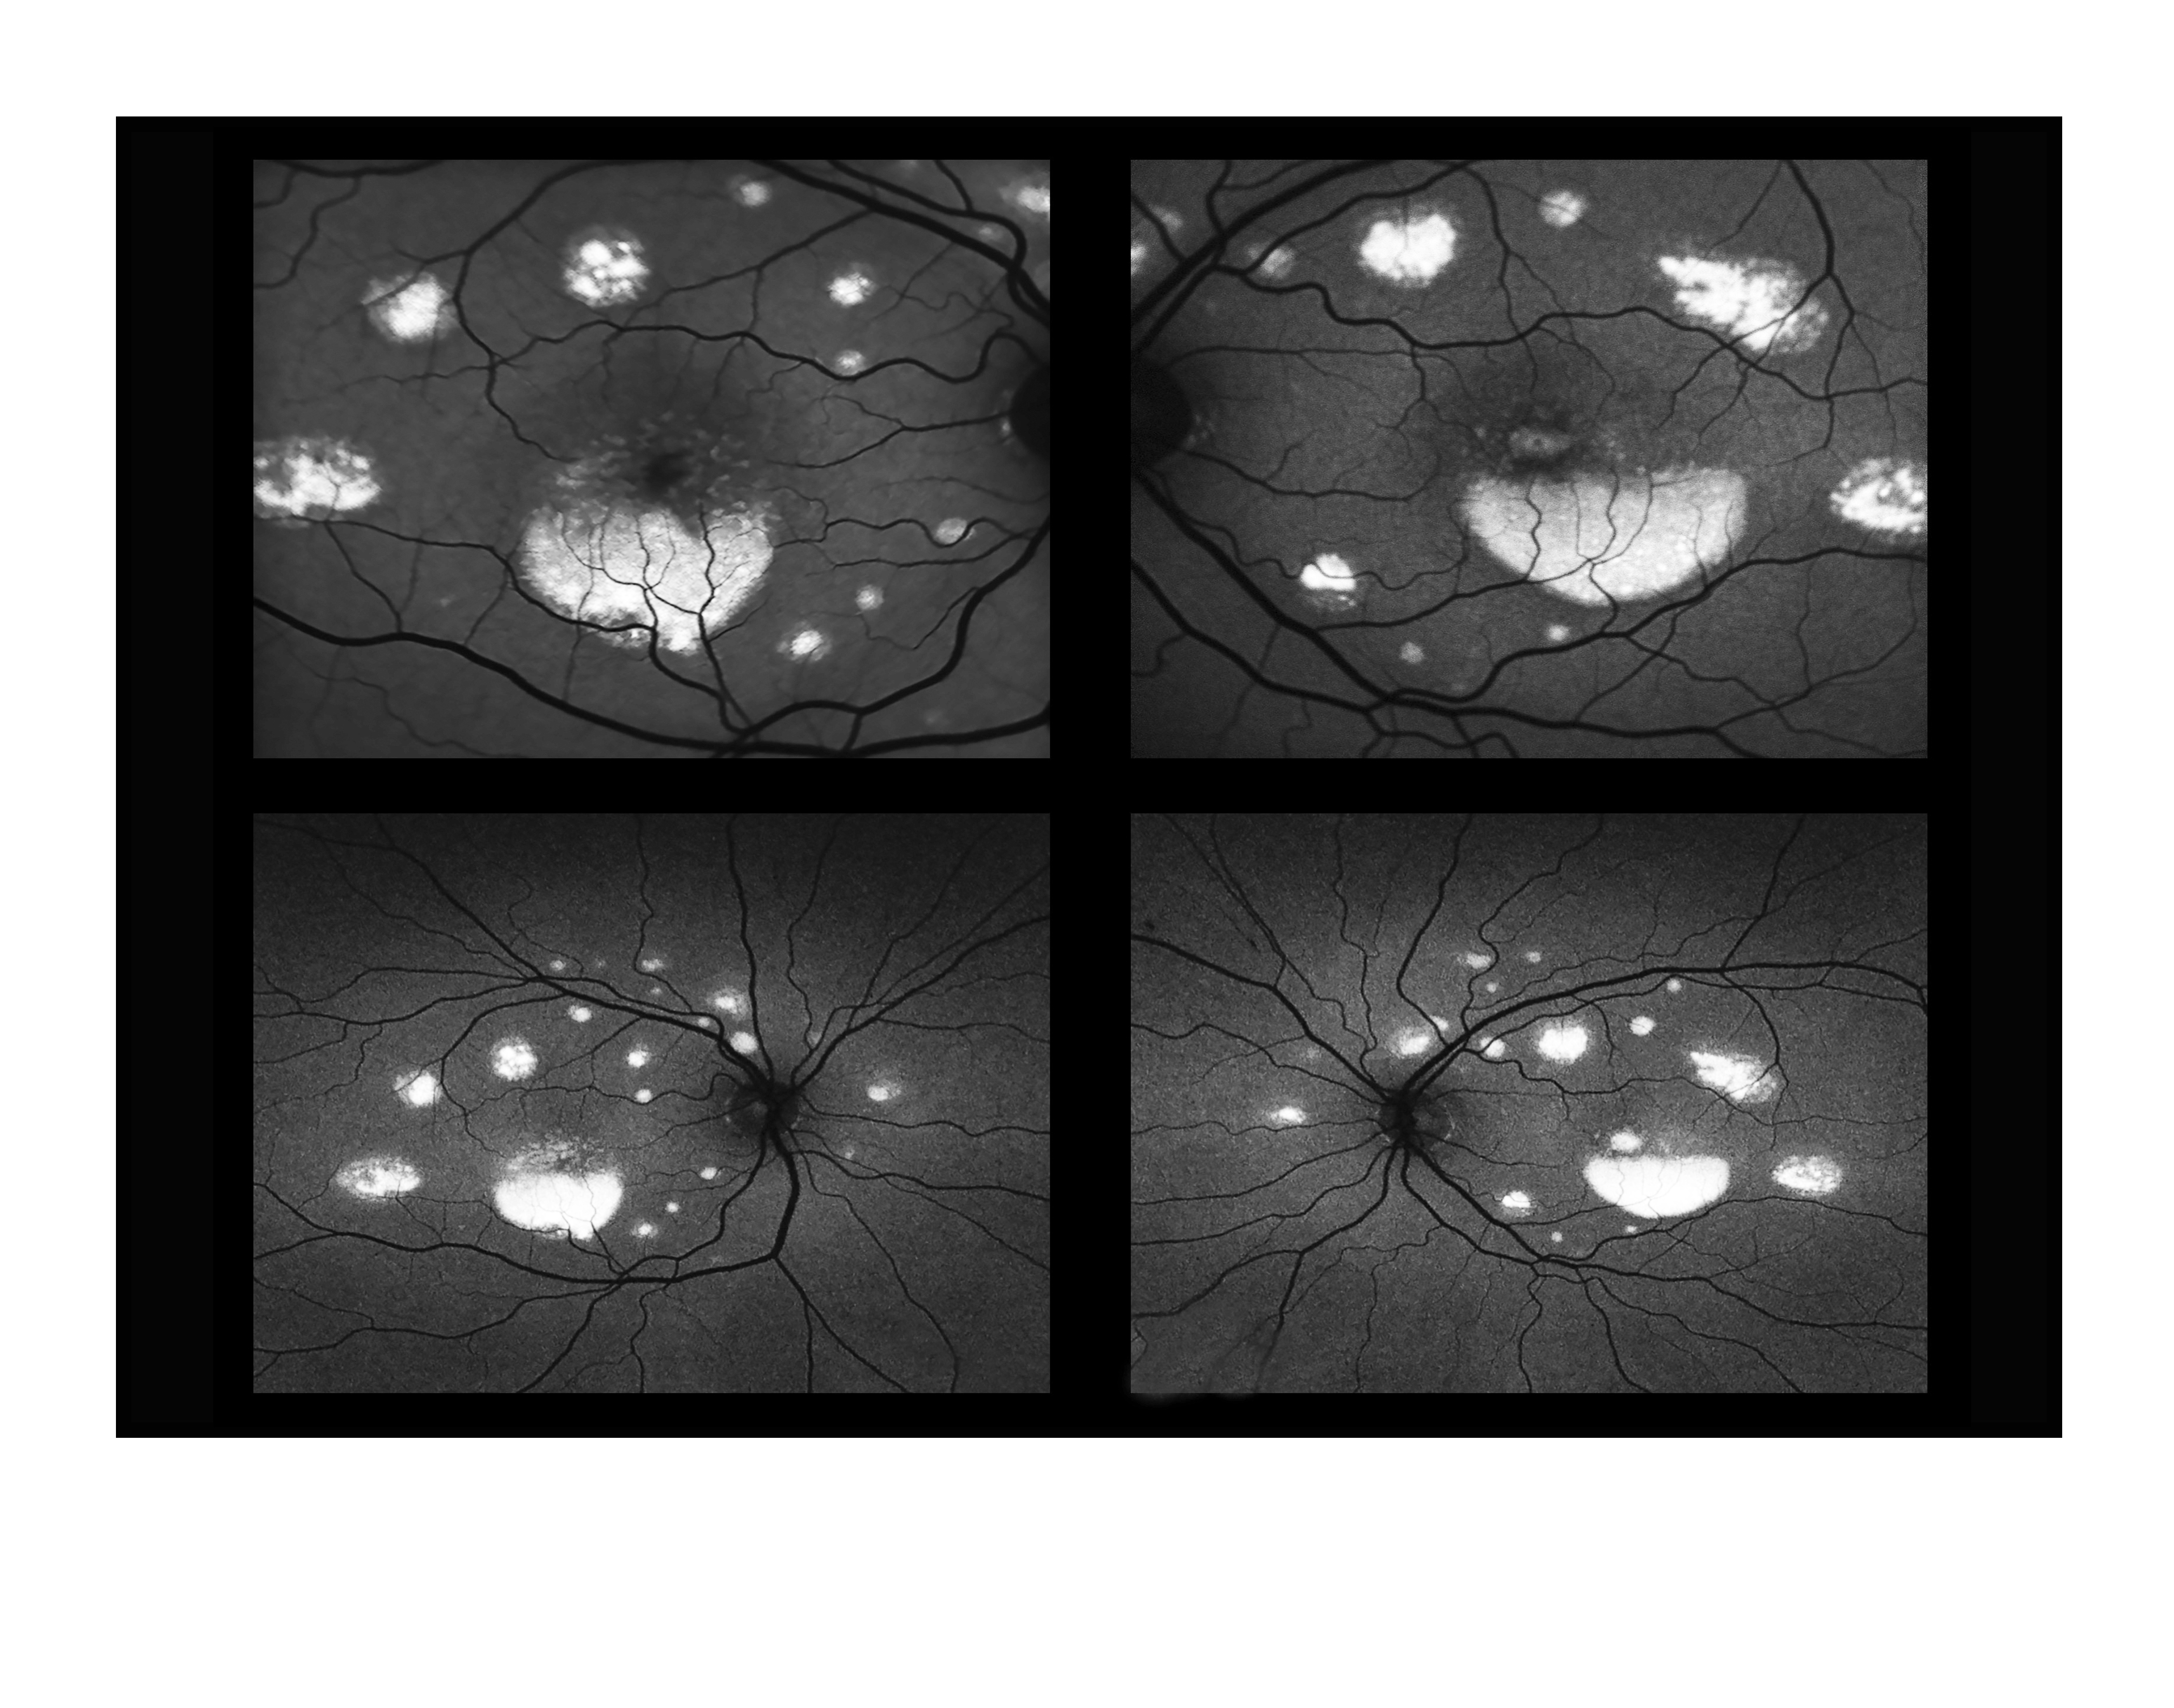

Exudative Polymorphous Vitelliform Maculopathy

Presented by Judith Gulian, OCT-C

This photograph received Third Place in the category "Fundus Autofluorescence" and was displayed in the 2024 OPS Exhibit.